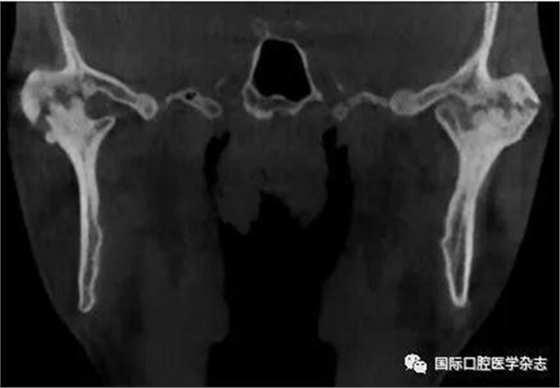

(4)關(guān)節(jié)強(qiáng)直(圖3):指因器質(zhì)性病變導(dǎo)致長(zhǎng)期開口困難或完全不能開口??煞譃殛P(guān)節(jié)內(nèi)強(qiáng)直和關(guān)節(jié)外強(qiáng)直。關(guān)節(jié)內(nèi)強(qiáng)直是由于一側(cè)或兩側(cè)關(guān)節(jié)內(nèi)發(fā)生病變,造成關(guān)節(jié)內(nèi)的纖維性或骨性粘連,也有人稱為真性關(guān)節(jié)強(qiáng)直。關(guān)節(jié)外強(qiáng)直是病變位于關(guān)節(jié)外上下頜間皮膚、黏膜或深層肌肉組織,形成頜間瘢痕攣縮(圖4),也有人稱為假性關(guān)節(jié)強(qiáng)直[7]。5)顳下頜關(guān)節(jié)感染:常由下頜關(guān)節(jié)附近化膿性病灶所致。多見于兒童中耳炎、腮腺炎等。此外還可由全身性傳染性疾病如麻疹、猩紅熱等引起。6)顳下頜關(guān)節(jié)外傷(圖5):外傷是引起開口受限的常見因素之一,最常見于下頜骨髁突骨折引起下頜運(yùn)動(dòng)受限[8]。

圖 3 關(guān)節(jié)內(nèi)強(qiáng)直